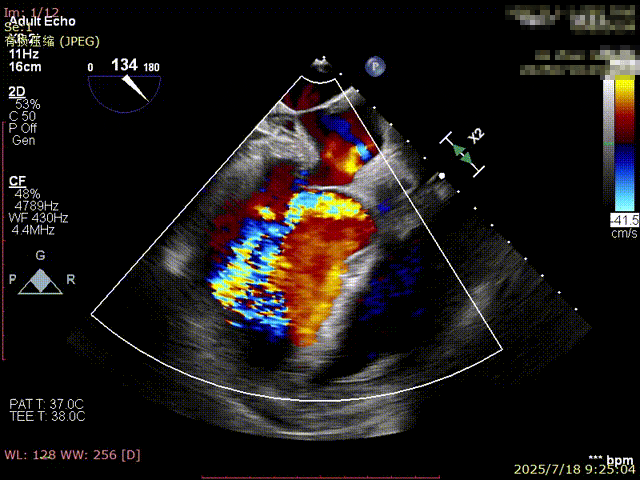

术前超声

术后超声